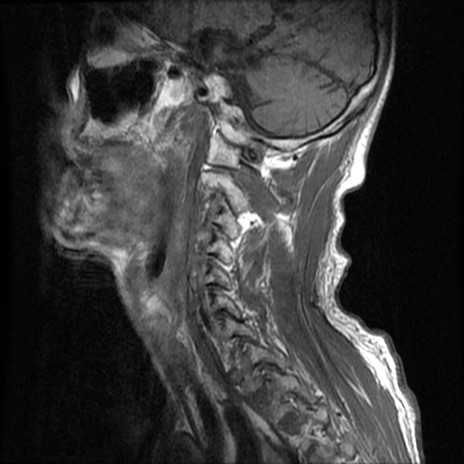

症例46 頚椎MRI T1WI(矢状断像)

【症例】80歳代男性

【主訴】両側頚部〜上肢のしびれ

【現病歴】昨日、自宅内で転倒、その後より上記症状あり。意識障害なし。

【身体所見】両側上肢のallodynia(熱痛覚過敏)あり。MMTおよびDTRは正確な所見取れず。両上肢の挙上はなんとか可能。

異常所見と診断は?

頚椎MRI

T2WI(矢状断像)